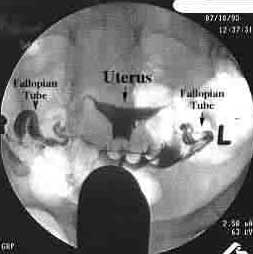

Хистеросалпингография или ХСГ е специализирана рентгенограма на матката и тръбите. ХСГ се прави след края на менструалния цикъл – обикновено на 6 или 7 ден от цикъла, когато лигавицата на матката е тънка. Прави се в рентгенова клиника. много лекари съветват пациентката да вземе антибиотик и болкоуспокояващо преди процедурата. След като бъде настанена на рентгеновта маса, лекарят поставя специален инструмент в цервикса, наречен цервикална канюла, която е метална. Много лекари сега предпочитат да използват балонен катетър, тъй като това прави процедурата по-безболезнена. След това, в маточната кухина се инжектира радио-непроницаема боя (течност, която е непроницаема за рентгеновите лъчи). Това се прави бавно под налягане и се правят снимки – за предпочитане под усилвател на изображенията. Преминаването на боята през маточната кухина, после през тръбите и от там в коремната кухина, може да бъде видяно и да се снима на рентген. Това осигурява дълготрайно документиране.

Поне 3 снимки трябва да бъдат направени, за да се подсигурят надеждни сведения – включително ранна снимка от маточната кухина и снимка, на която да се уверим, че течността свободно се излива в коремната кухина.

Нормалната ХСГ определя вътрешността на репродуктивния тракт. Той изглежда като триъгълник (обикновено бял на черен фон), който изобразява маточната кухина; и от тук течността влиза в тръбите, което се вижда като две дълги тънки линии, по една от всяка страна на кухината. Когато боята изтече в коремната кухина от проходимата тръба, това се визуализира на рентгена като петно.

Фиг.2. Нормални находки от ХСГ (боята изглежда черна и очертава нормална кухина и фалопиеви тръби)

Необичайна ХСГ може да покаже проблем в маточната кухина – и това се вижда като пролука или дефект при изпълването. Все пак, най-чести проблеми при ХСГ се появяват в тръбите. Ако тръбите са запушени в частта на истмуса (където се съединяват с матката), боята не прониква в тях и те изобщо не могат да бъдат видени. Ако запушването е откъм фимбриалния апарат, тръбите се изпълват, но боята не се излива в коремната кухина и краят на тръбите често е издут.

Понякога, както всяко друго медицинско изследване, хистеросалпингографията може да покаже грешни резултати. Например, стената на матката може да направи спазъм, в резултат на което боята може изобщо да не нахлуе в тръбите. Това може да се интерпретира като запушване на тръбите, докато на практика, те са проходими. Също така, ако има много тънък хидросалпинкс боята е инжектирана под налягане, може да изглежда, течността че се излива в коремната кухина през разкъсване в стената на хидросалпинкса – което предполага проходимост на тръбите, докато реално те са запушени.